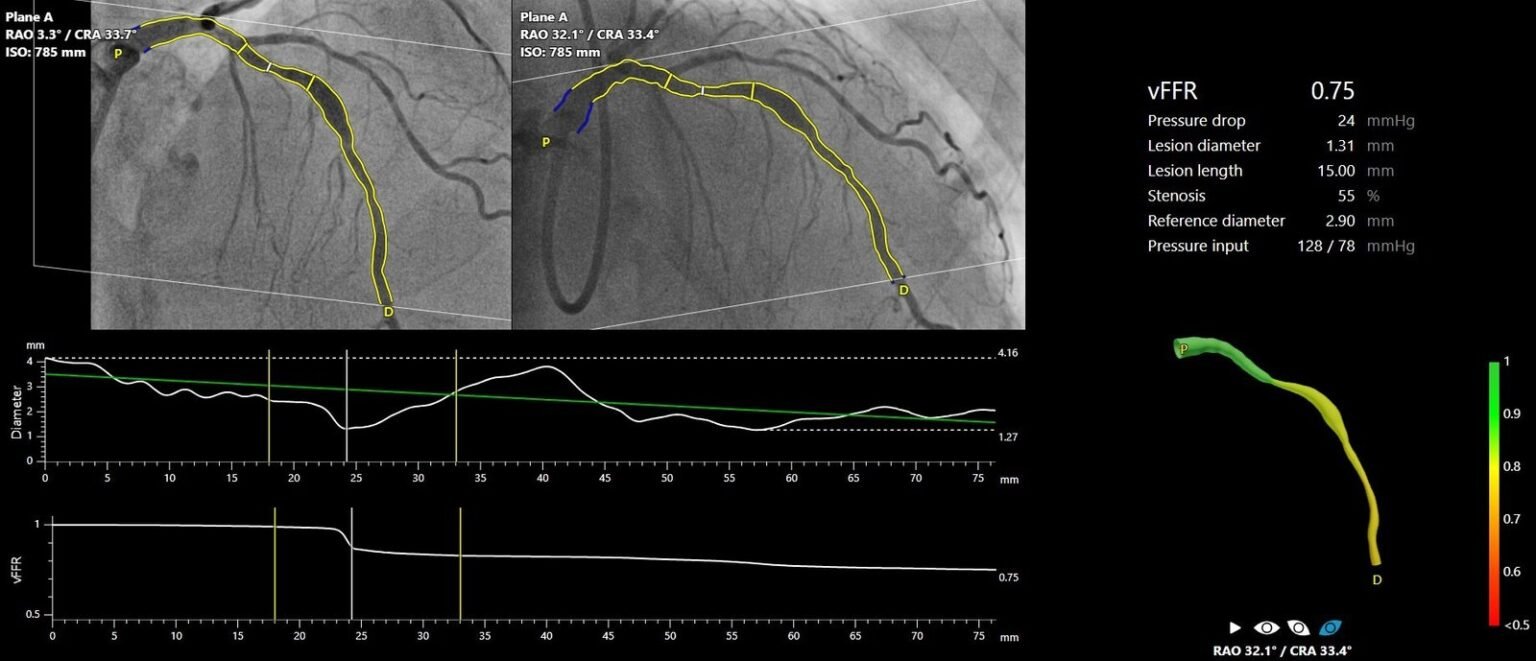

FAST III war eine vom Prüfarzt initiierte, offene, multizentrische, randomisierte Studie, in der eine vFFR-geführte mit einer FFR-geführten Koronarrevaskularisation bei 2235 Patienten mit intermediären Koronarläsionen (definiert als 30-80%ige Stenose durch visuelle Beurteilung oder QCA) verglichen wurde. Intermediäre Läsionen wurden physiologisch anhand von vFFR oder FFR auf der Tischseite beurteilt und behandelt, wenn vFFR oder FFR ≤0,80 waren. Der primäre Endpunkt war ein Kompositum aus allen Todesursachen, einem Myokardinfarkt oder einer Revaskularisierung 1 Jahr nach der Randomisierung.

„Die Ergebnisse von FAST III bestätigen die Sicherheit und Machbarkeit des Online-Einsatzes der vFFR als einfaches, minimal-invasives Instrument zur Anleitung der Revaskularisation bei Patienten mit intermediären Koronararterienläsionen, die eine physiologische Beurteilung der Läsion benötigen. Die Technologie hat das Potenzial, den Einsatz der Physiologie zu verstärken, was die Prognose von Patienten verbessern könnte, bei denen die Entscheidung zur Revaskularisierung intermediärer Koronararterienläsionen immer noch weitgehend auf Augenmaß beruht. Der Einsatz der vFFR macht Führungskatheter, invasive Koronararterieninstrumente und hyperämische Wirkstoffe überflüssig, die mit Risiken und Unannehmlichkeiten für den Patienten verbunden sind„, so Dr. Joost Daemen.